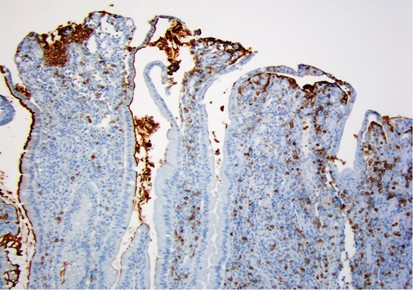

Figure 4

CD10 staining in an ileal pouch that was resected for chronic, treatment-refractory pouchitis. Blunted villi have a mixture of positive staining (left) and almost completely negative epithelium (right).